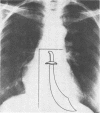

Anomalous pulmonary venous drainage to the inferior vena cava is a rare congenital cardiac defect. Oxygenated blood from the right lung enters the right atrium resulting in a left-to-right shunt. Because the radiographic shadow of the anomalous vein resembles a curved saber, this defect has been called the “scimitar” deformity. From 1958 through June 30, 1975, 11 patients underwent surgical correction of this anomaly at our institution with 10 survivors. Diagnosis was made by routine roentgenography of the chest in all but one patient. Eight patients had total correction which consisted of implanting the anomalous vein into the right atrium, opening the interatrial septum and applying a patch graft as a baffle to direct pulmonary venous blood into the left atrium. Five patients had associated cardiac defects which were also repaired. Three patients underwent pneumonectomy and all survived. The only operative death occurred in a 5-year-old female with an atrial septal defect and endocardial cushion defect. We believe the existence of a large left-to-right shunt justifies surgical intervention. The prognosis appears to depend upon the presence of other cardiac or pulmonary anomalies.